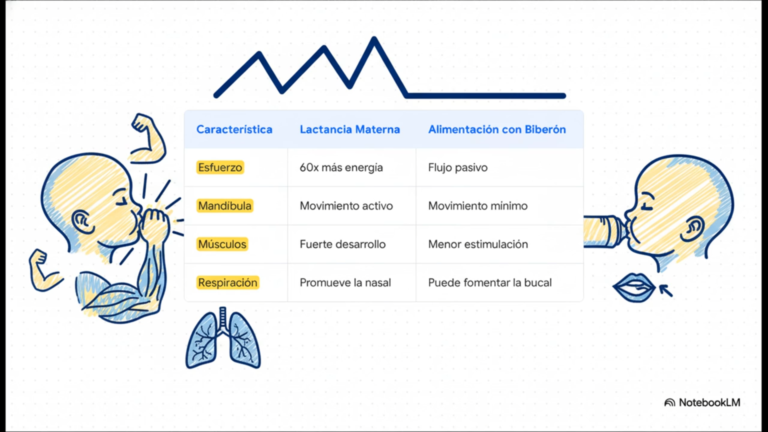

La Lactancia Materna como Estímulo Funcional y Biomecánico en el Desarrollo del Complejo Craneofacial

La lactancia materna trasciende su rol como estándar nutricional e inmunológico; hoy se posiciona como el determinante principal en la maduración neuromuscular y el crecimiento del sistema estomatognático. La evidencia científica subraya que el acto de amamantar es una actividad motora compleja que coordina succión, deglución y respiración, actuando como el primer aparato de ortopedia…